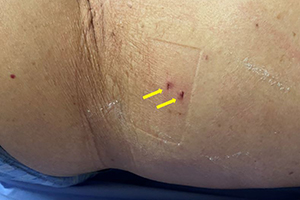

体外から専用の細い針で病変部を刺し、がんを壊死させる治療法です。

局所麻酔下にて行われ、傷痕が小さく出血も少ない体の負担が少ない治療法です。

腎がんに体外から病変に電極針を刺し、高周波の電磁波を流してがんを焼いて壊死させる治療法です。直径1.5mm程度の電極震を用い、1か所当たり5~10分程度通電させます。

穿刺部位はCTやエコーなどで厳密に調べた病変部位によって決定されます。